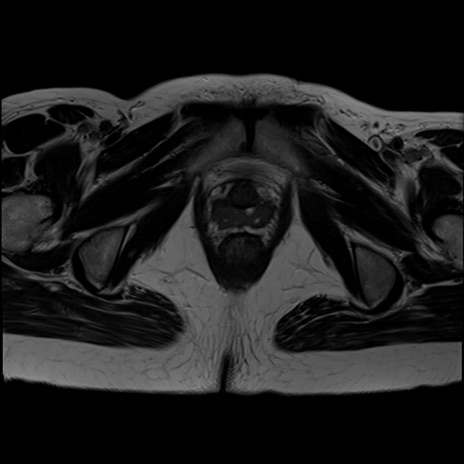

症例39 T2WI(横断像)

MRI(4日後)